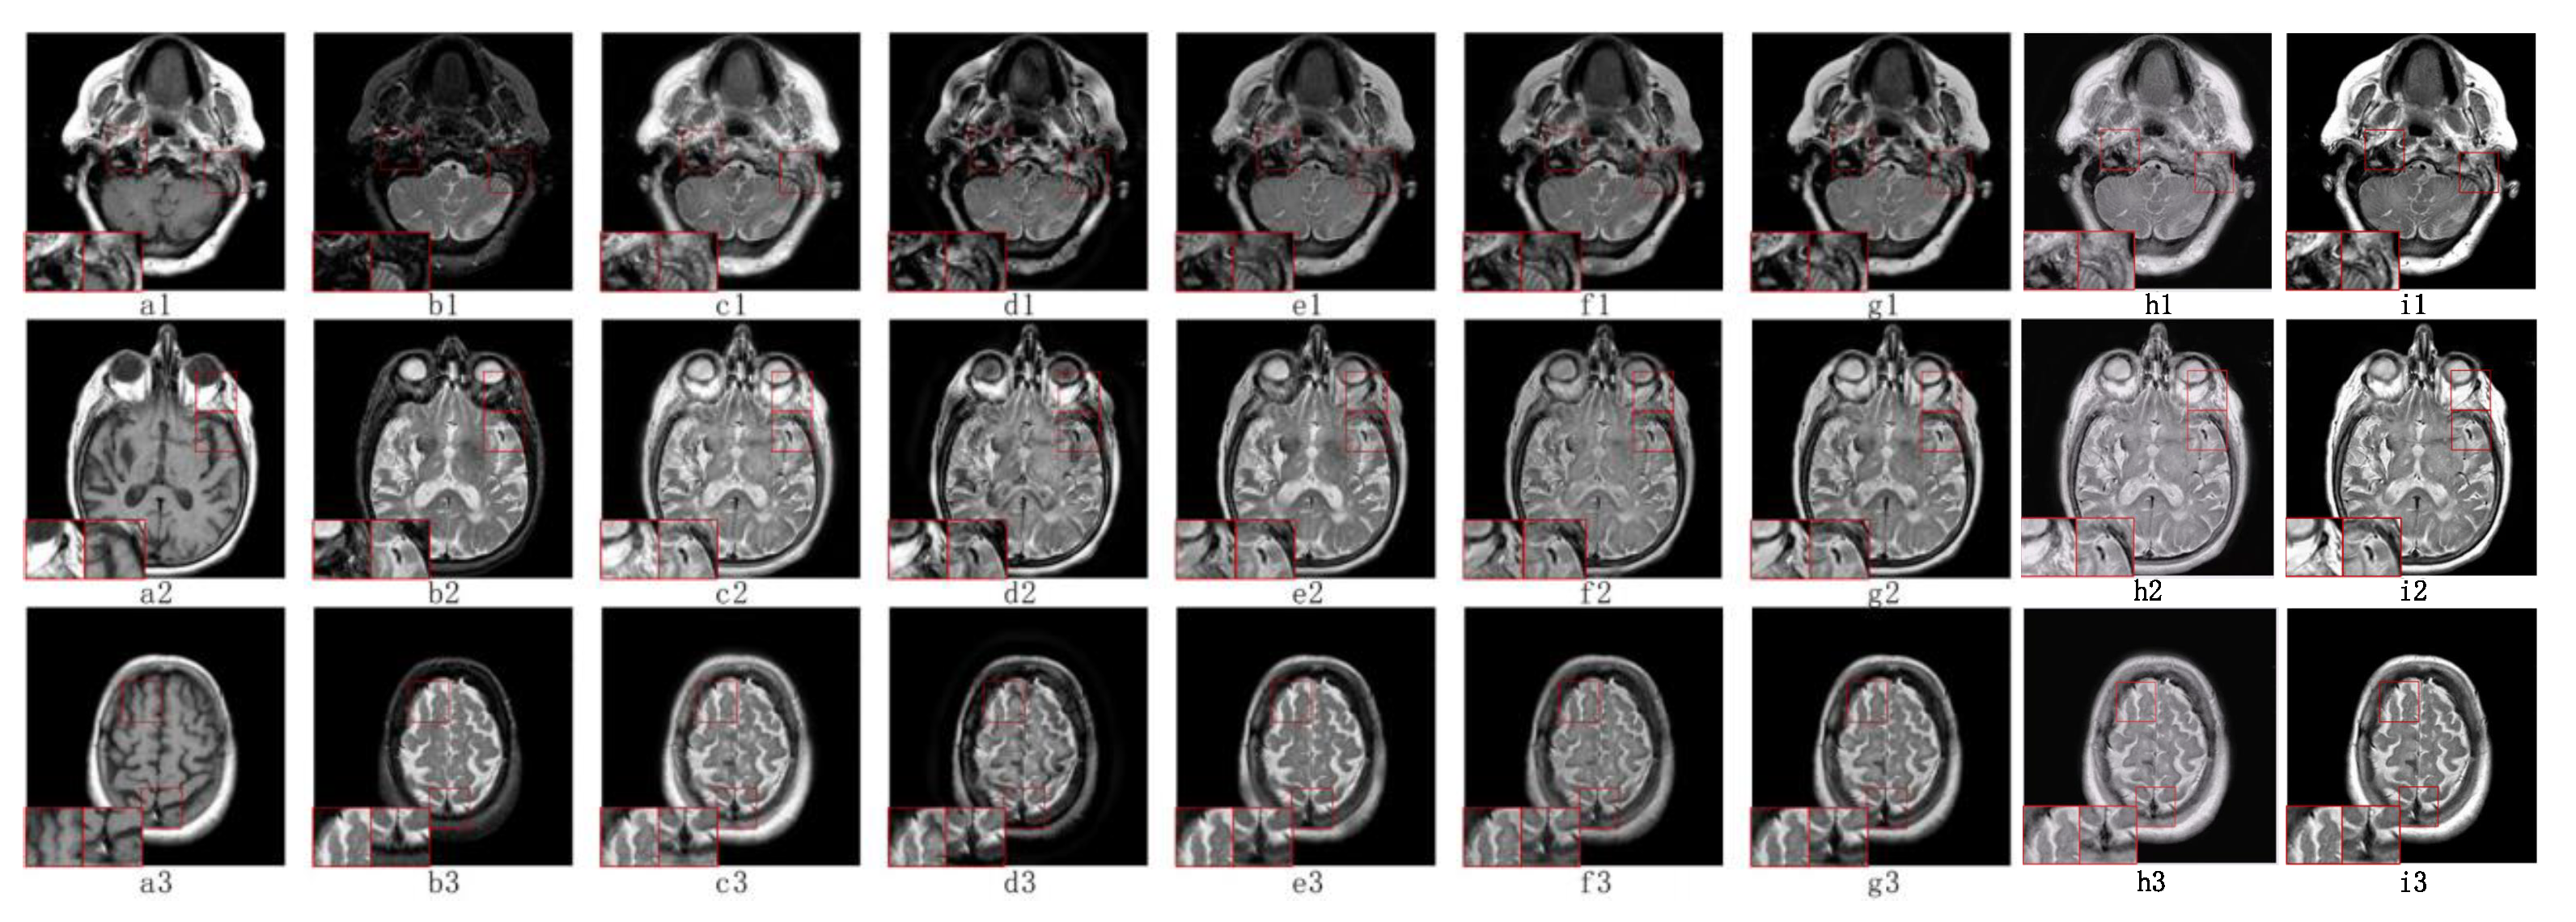

5.2. Visual Effects Analysis

5.2.1. Fusion Analysis on T1-T2

5.2.2. Fusion Analysis on T2-PD